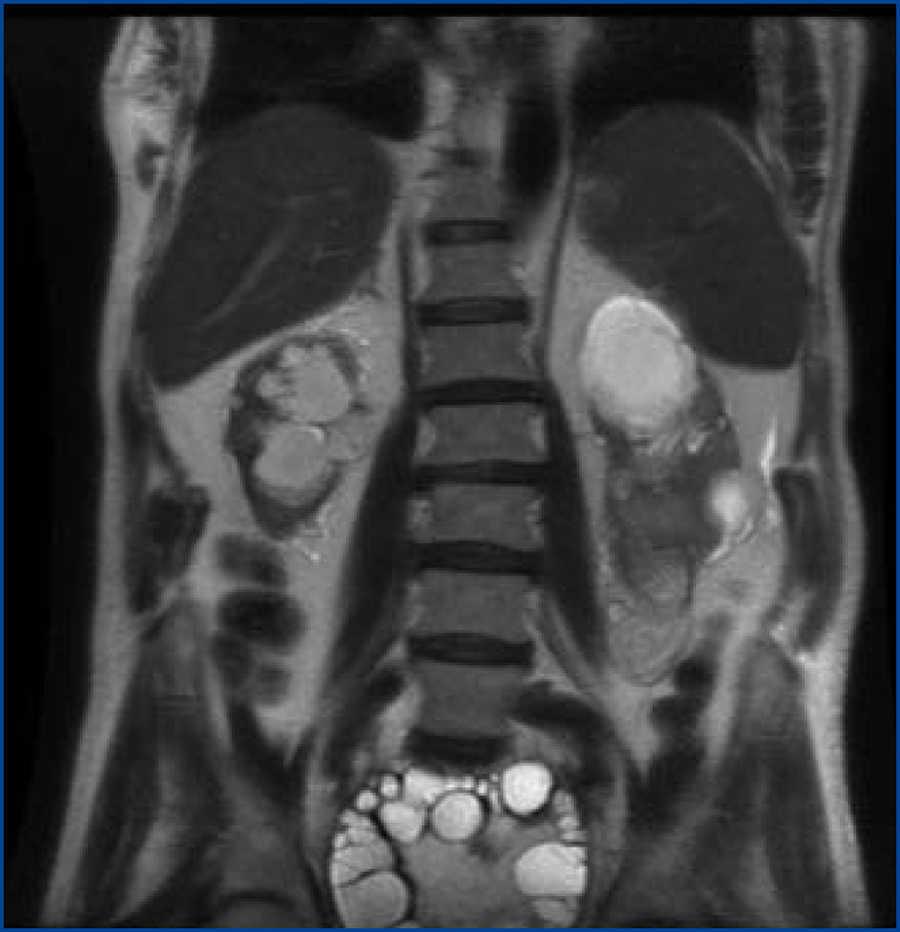

La resonancia magnética (figura 1) muestra una gran lesión ocupante de espacio de 17,5 cm de diámetro máximo que invade la cavidad pélvica con el polo superior a la altura de L4-L5, ejerciendo un colapso casi total de la vejiga. Tiene forma ovoidea, bien definida, con múltiples septos internos, compatible con quiste hidatídico tipo II2B de Polat. En polo inferior del RI se observa una lesión de 61 mm ovoidea compatible con quiste hidatídico inactivo tipo III. Hay dilatación de ambos sistemas colectores renales, con disminución del RD, que tiene un diámetro de 84 mm y cortical adelgazada. El RI tiene un diámetro longitudinal de 11 cm.

Figura 1. Resonancia magnética